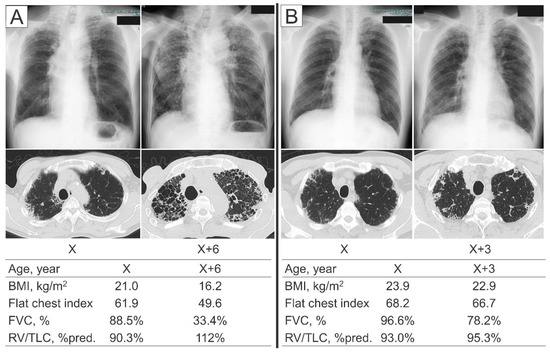

Among IPPFE patients who did not meet the physiologic criteria (n = 6), some came to meet the physiological criteria during the observation period (3/6, 50%), but others did not (3/6, 50%). Representative cases were shown in Figure 6. None of the IPPFE patients who met the physiological criteria at the time of the diagnosis deviated from the criteria during the observation period.

Figure 6.

Representative IPPFE patients who did not meet the physiologic criteria at the time of the diagnosis. (A) A 68-year-old man who came to meet the physiological criteria during the clinical course. Although the forced vital capacity (FVC) was relatively well preserved at the time of the diagnosis, he experienced a marked decline in the FVC over the six years from the diagnosis, accompanied by decreases in the body mass index (BMI) and flat chest index and an increase in the percentage of the predicted values of residual volume/total lung capacity (RV/TLC %pred.). (B) A 68-year-old man who did not meet the physiological criteria during the observation period. The FVC was relatively well preserved at the time of the diagnosis as well as three years after the diagnosis. The BMI, flat chest index, and RV/TLC %pred. did not change markedly during the three years.